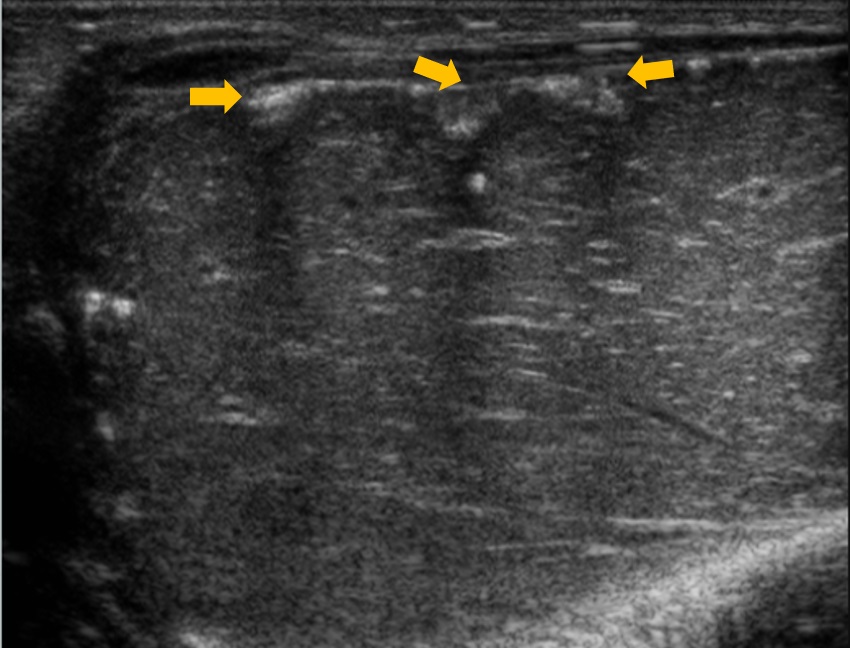

Al nacimiento se confirma la presencia de al menos cuatro imágenes nodulares de pequeño tamaño, hiperecogénicas, en ambos lóbulos hepáticos (Fig. 2). Sin alteración de enzimas hepáticas en la analítica sanguínea. Ecocardiograma y ecografía transfontanelar sin hallazgos significativos.

| Figura 2. Hiperecogenicidad intrahepática con sombra posterior, compatible con calcificación hepática |